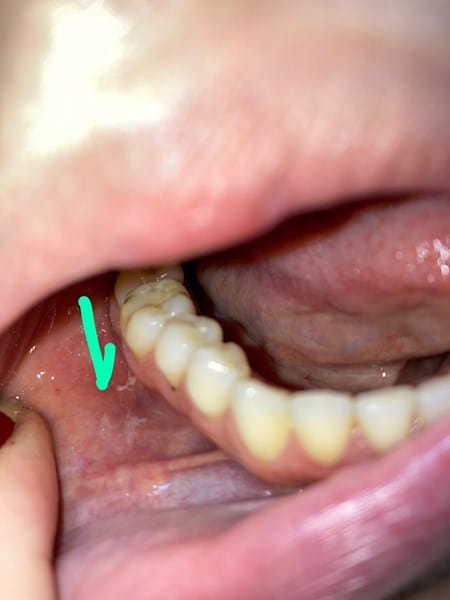

Hace una semana tengo unas molestias en mi boca, primero bajo mi lengua se formaron como unas laceraciones con aspecto algo blanco y en mis mejillas dos aftas de color rojo, he estado tomando fluconzaol y haciéndome baños de agua sal pero no se si quizá sea otra cosa, pienso empezar esta semana con nistatina, no me duelen las aftas de las mejillas se sienten como elevadas y algo ásperas al tacto he leído que la candidiasis da también en aftas rojas y además me da muy frecuente candidiasis vaginal. Gracias